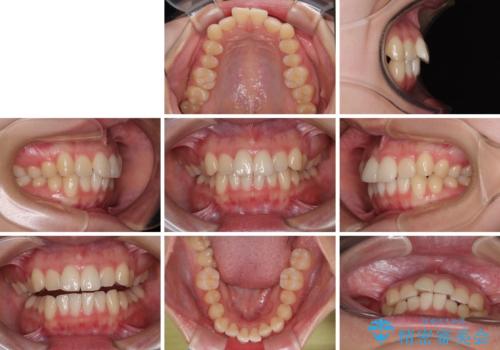

- 上下前歯のデコボコを気にして来院された患者様です。

ワイヤー矯正でもマウスピース矯正でも可能でしたが、短期間で、自身の手を煩わせることなく治療を行いたいとのことで、ワイヤー装置にて矯正治療を行うこととしました。

舌の突出癖により、出っ歯仕上がりとなる可能性がありましたが、舌のトレーニングを頑張っていただき、1年強で終えることができました。